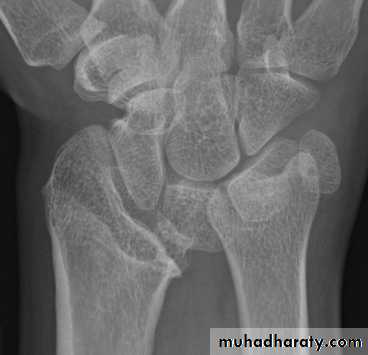

• Septic arthritis2. Chronic osteomyelitis.

Septic arthritis

especially in intraarticular metaphyses ( sholder , elbow , hip)